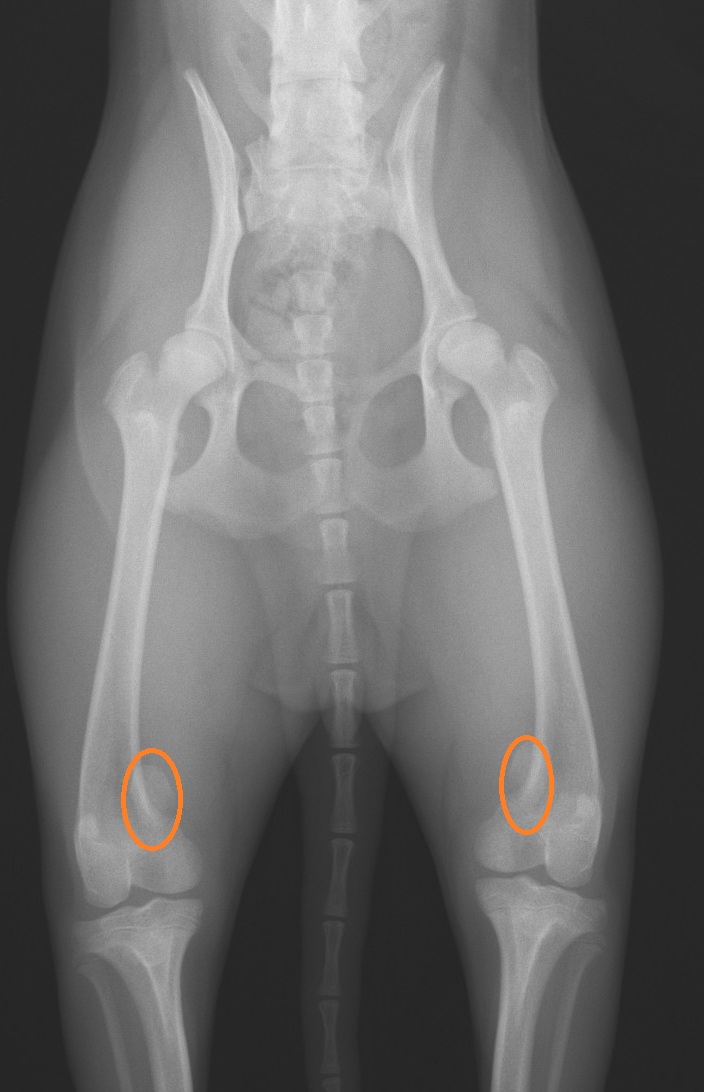

上の写真は、

犬を仰向けにして撮影したレントゲン写真で、

中央に骨盤、そこから大腿骨、脛骨が写っています。

膝蓋骨はというと

オレンジの丸印をつけた

楕円の骨です。

その膝蓋骨が、

大腿骨(太ももの骨)の真上にないといけないのが、

両方ともに内側にずれてしまっています。